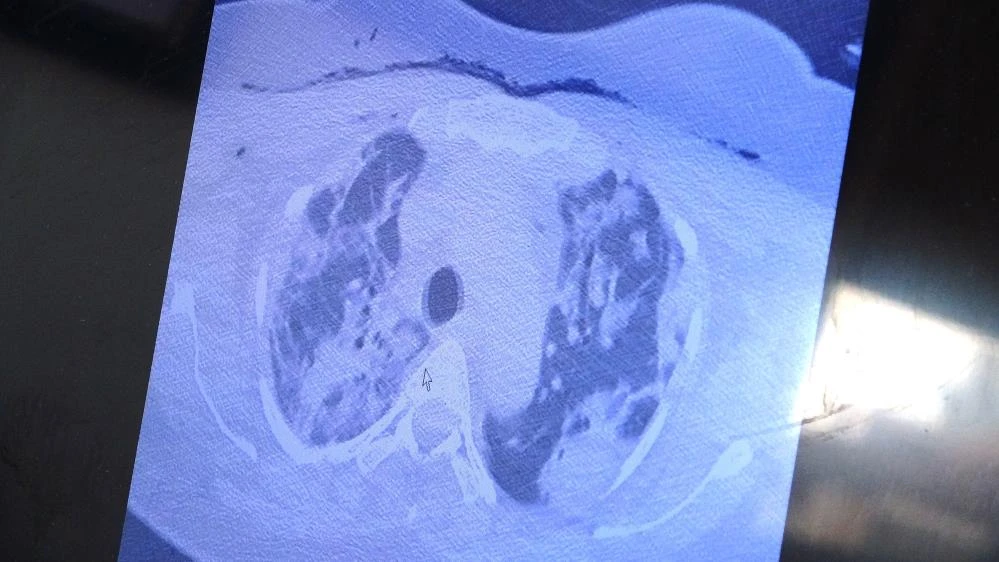

Yurt dışından kendisine gelen ve bebeği ile annesini hayata tutunmasını sağlayan Özkaya, "Bu yurt dışında hamileyken kovide yakalan ve ciddi akciğer tutulumu olan 38 yaşında hastamız var. Tedavi olmak için bizim ülkemize geldi. Ciddi solunum yetmezliği vardı. Biz hem annenin hem de bebeğin hayatını garanti altına almak için bebeği aldık. Sağlıkla doğum yaptı. Annenin akciğerine tomografi çektik. Ciddi akciğer tutulumu, ciddi harabiyet olduğunu tomografisinde gördük. Geçen yıllarda gebelerde böyle tutulumlar yoktu" ifadelerini kullandı.